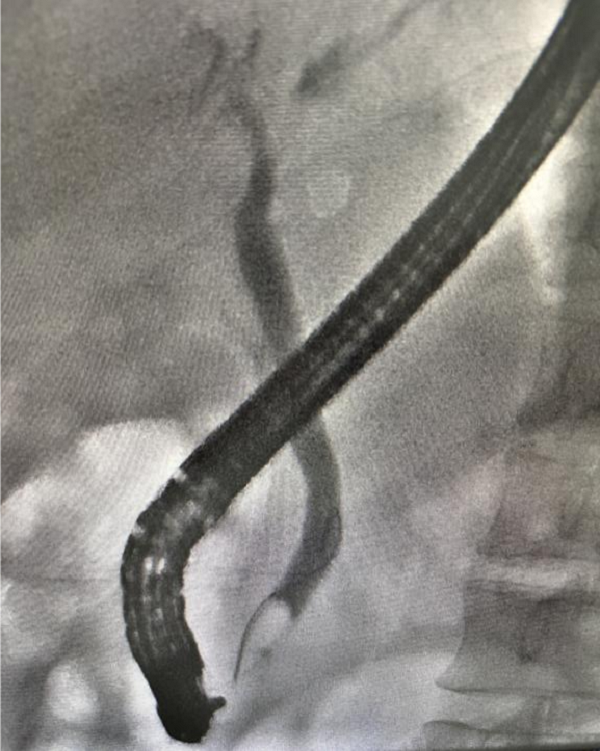

1. 内镜逆行胆管造影(ERC)术:一名中年男性因“反复上腹部疼痛不适3个月余,再发4天”入院。外院肝胆脾胰彩超+腹部CT+MRCP检查诊断“胆总管结石伴胆管炎”明确。患者为寻求微创手术转入我院。完善术前检查,经综合评估,在静脉全麻下行内镜逆行胆管造影(ERC)术,术中发现结石大小约0.6cm*0.6cm,遂做内镜下奥狄氏括约肌扩张术,未做奥狄氏括约肌切开,保留奥狄氏括约肌功能,并顺利取出结石。患者术后无明显并发症,恢复顺利。